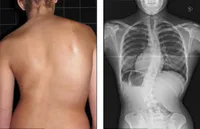

La siguiente fractura se hizo en que parte de este hueso

Cuello anatómico del humero derecho

Cuello quirúrgico del humero derecho

Cuello anatómico del humero izquierdo

Cuello quirúrgico del humero izquierdo